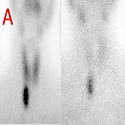

Localisation osseuse sternale et claviculaire d’une amylose

Neirouz Ghannouchi Jaafoura, Amira Atig

PAMJ. 2014; 19: 94. Published 26 September 2014